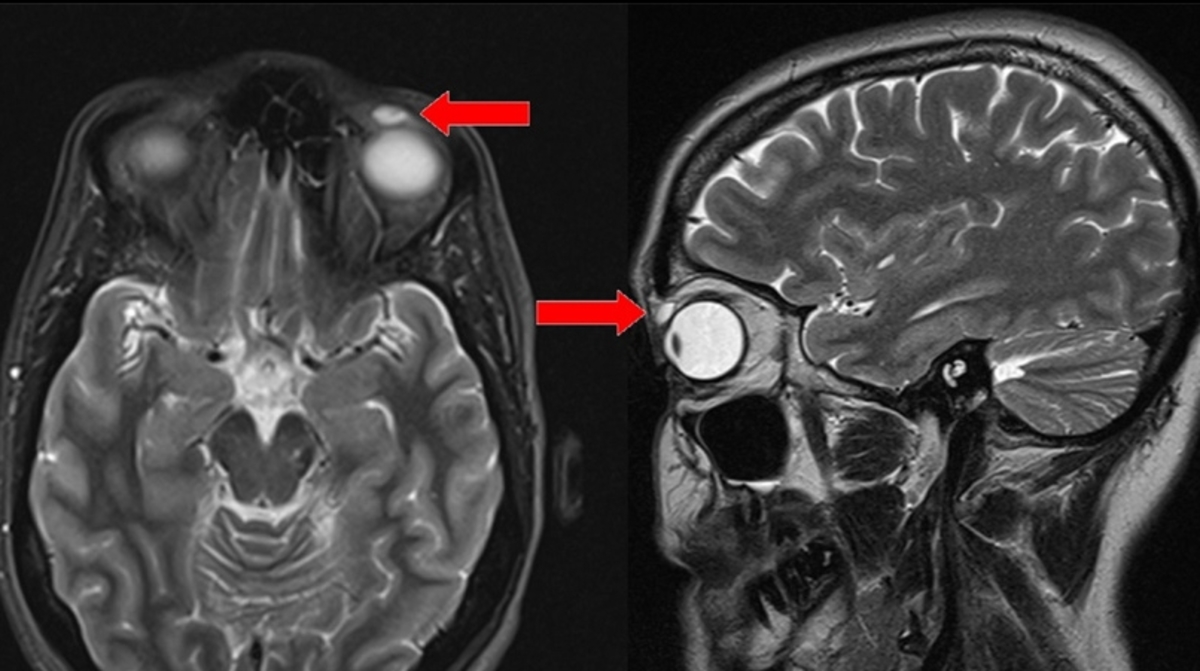

Ναι, καλά διαβάσατε. Οι οφθαλμίατροί της αναφέρουν λεπτομερώς την περίπτωση αυτή σε άρθρο που δημοσιεύθηκε στην επιστημονική επιθεώρηση BMJ Case Reports. Η γυναίκα είχε πρήξιμο και βλεφαρόπτωση του άνω αριστερού βλεφάρου της για περίπου έξι μήνες, προτού ο γενικός της γιατρός την παραπέμψει σε οφθαλμίατρο. Οι συγγραφείς της μελέτης αναφέρουν ότι μια μαγνητική τομογραφία αποκάλυψε μια μικρή κύστη, η οποία στην συνέχεια απομακρύνθηκε χειρουργικά.

Ένας φακός επαφής είχε προκαλέσει την κύστη

Τότε ακριβώς, το πράγμα άρχισε να γίνεται πραγματικά… ενδιαφέρον. “Κατά την αφαίρεση, η κύστη έσπασε και ένας σκληρός φακός επαφής βγήκε από μέσα της! Το ξένο σώμα ήταν εξαιρετικά εύθραυστο κατά την αφαίρεση και τον χειρισμό. Αργότερα επιβεβαιώθηκε ότι πρόκειται για φακό τύπου RGP», αναφέρεται στην δημοσίευση. Το RGP προέρχεται από τα αρχικά rigid gas permeable, δηλαδή πρόκειται για αυτό που πριν αρκετά χρόνια ορίζαμε ως “σκληρός φακός επαφής». Επρόκειτο για σκληρό φακό που επέτρεπε, ωστόσο, στο οξυγόνο να φθάσει στην επιφάνεια του ματιού.